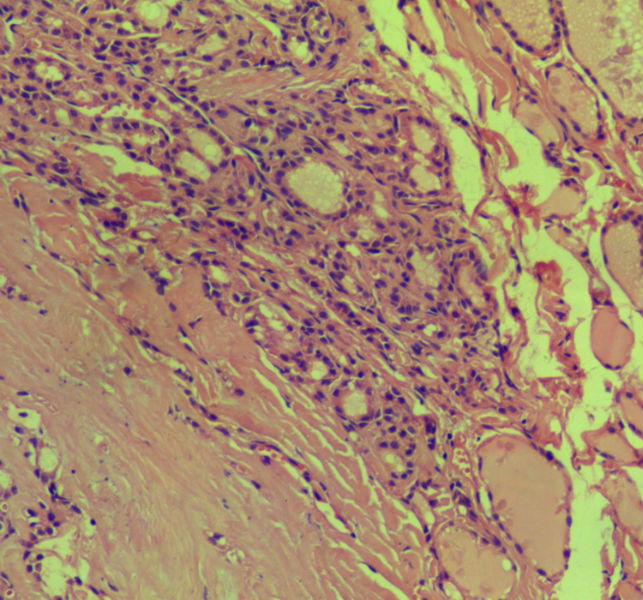

女,45岁,体检发现颈前区一结节,术中送检甲状腺左腺叶,发现一界清结小1*0.8cm,灰黄色。术中诊断滤泡性肿瘤伴包膜累及,局部疑包膜穿破,滤泡癌可能,待石蜡报告。石蜡连续切片形态见图,可见明显包膜穿破,诊断为滤泡性癌。患者借片到上级医院会诊,结果为:包膜内滤泡癌伴包膜累及。请问有包膜内滤泡癌的提法吗?这个病例怎么诊断啊?请各位老师多指导。

• 这个是滤泡性癌吗图3

图3

甲状腺滤泡癌确实分2型:浸润型包膜不完整,明显浸润周围甲状腺组织;包裹性血管浸润型有包膜,但有血管或包膜浸润。

本例包膜不完整,应该是滤泡癌。